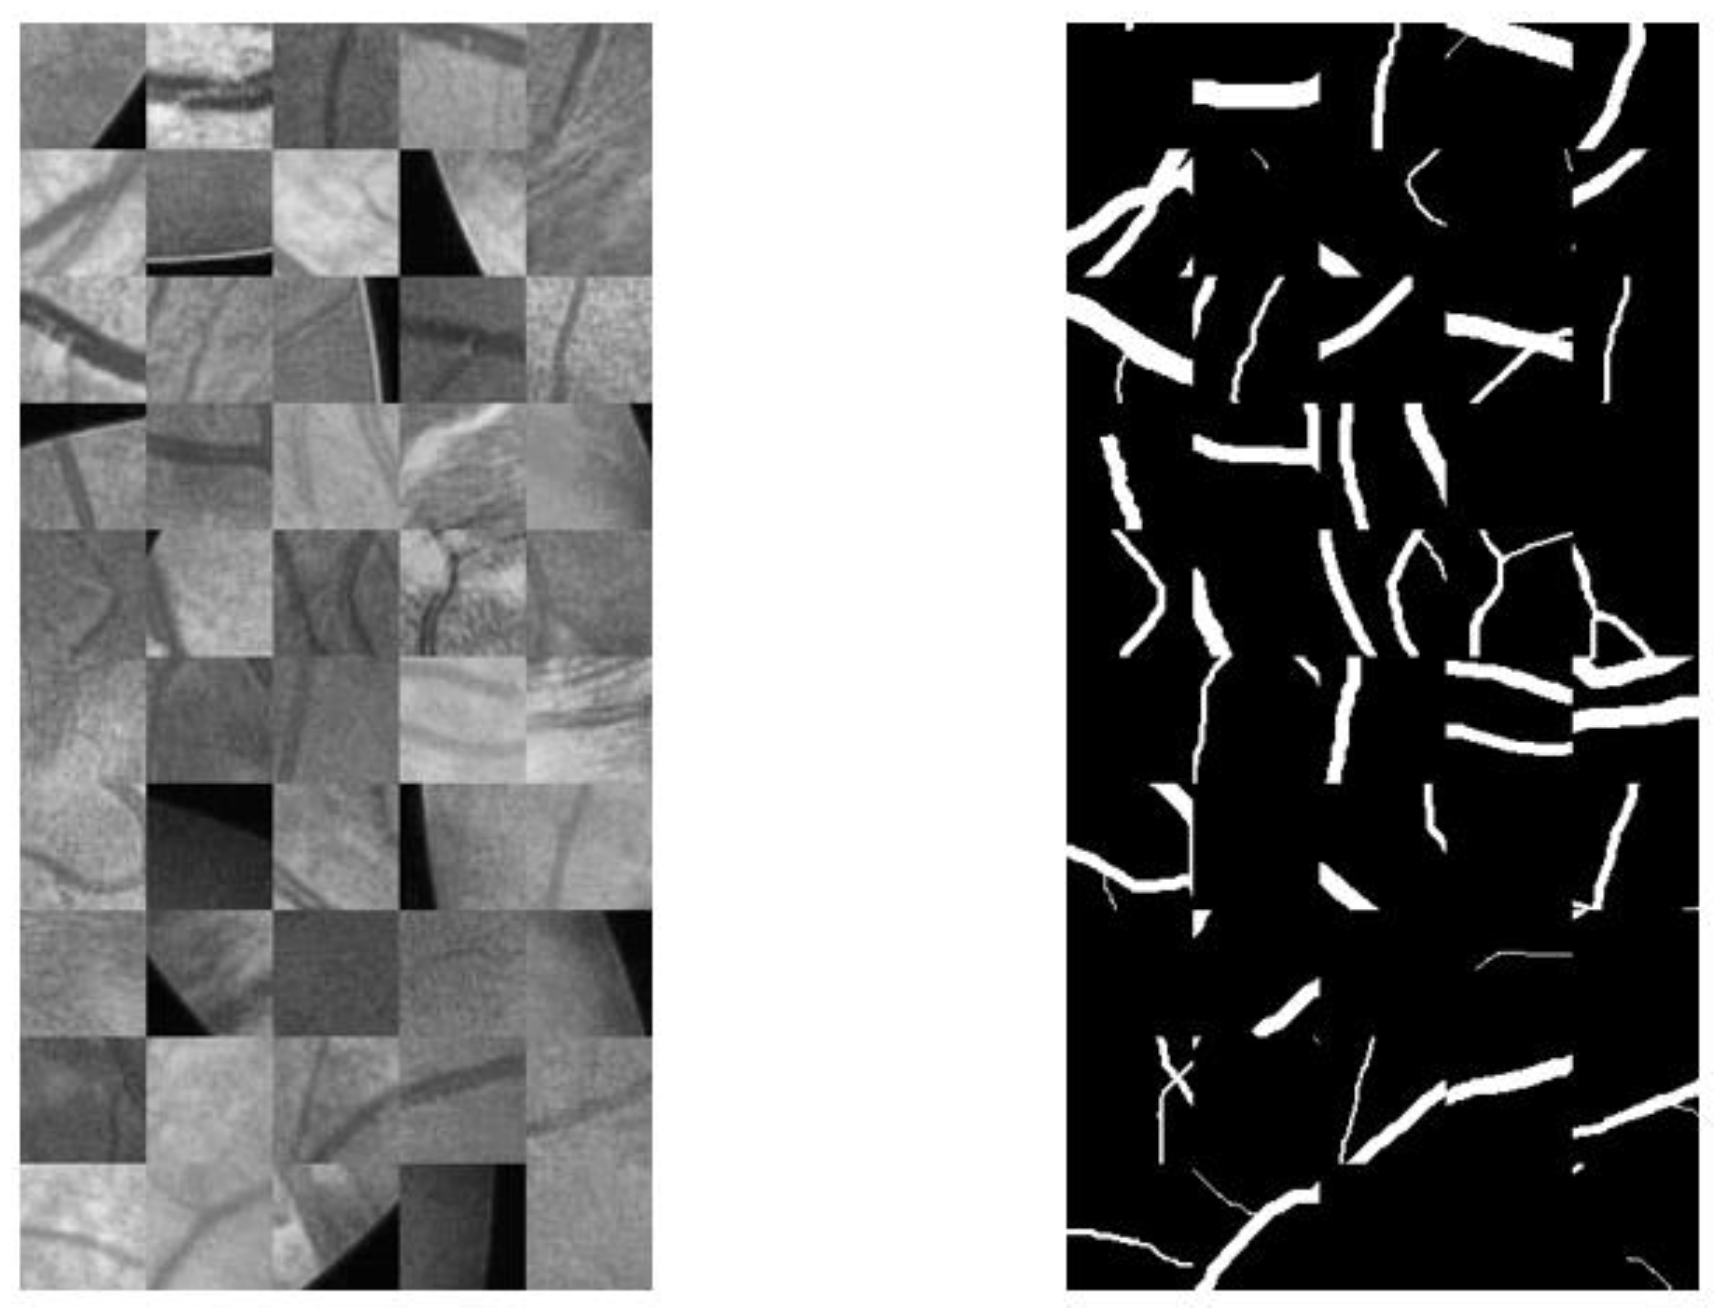

4.1.3. Data Augmentation

| Datasets | Original Image | Gold Standard Image | Mask Image |

|---|---|---|---|

| CHASEDB1 | ![]() | ![]() | ![]() |

| DRIVE | ![]() | ![]() | ![]() |